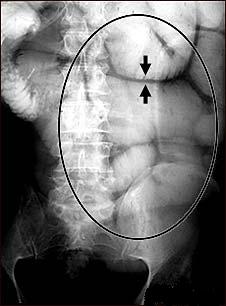

Ocluzia intestinala sau blocarea intestinului